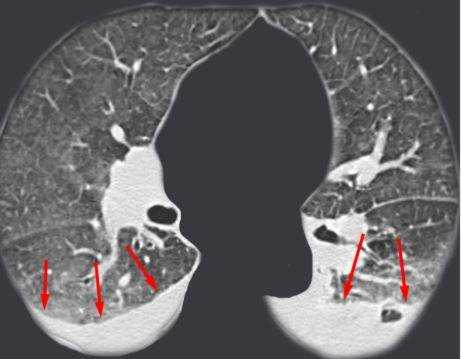

КТ без контраста у пациента с интерстициальным заболеванием легких в анамнезе и трансплантацией правого легкого показывает суженный участок анастомоза правого бронха (красная стрелка). Собственное левое легкое уменьшено в размерах, с признаками бронхоэктазов, бронхиолоэктазов (черная стрелка). Сужение центрального дыхательного пути на выдохе у трансплантированного легкого (синяя стрелка).

Выпот (красные стрелки) в обеих плевральных полостях.